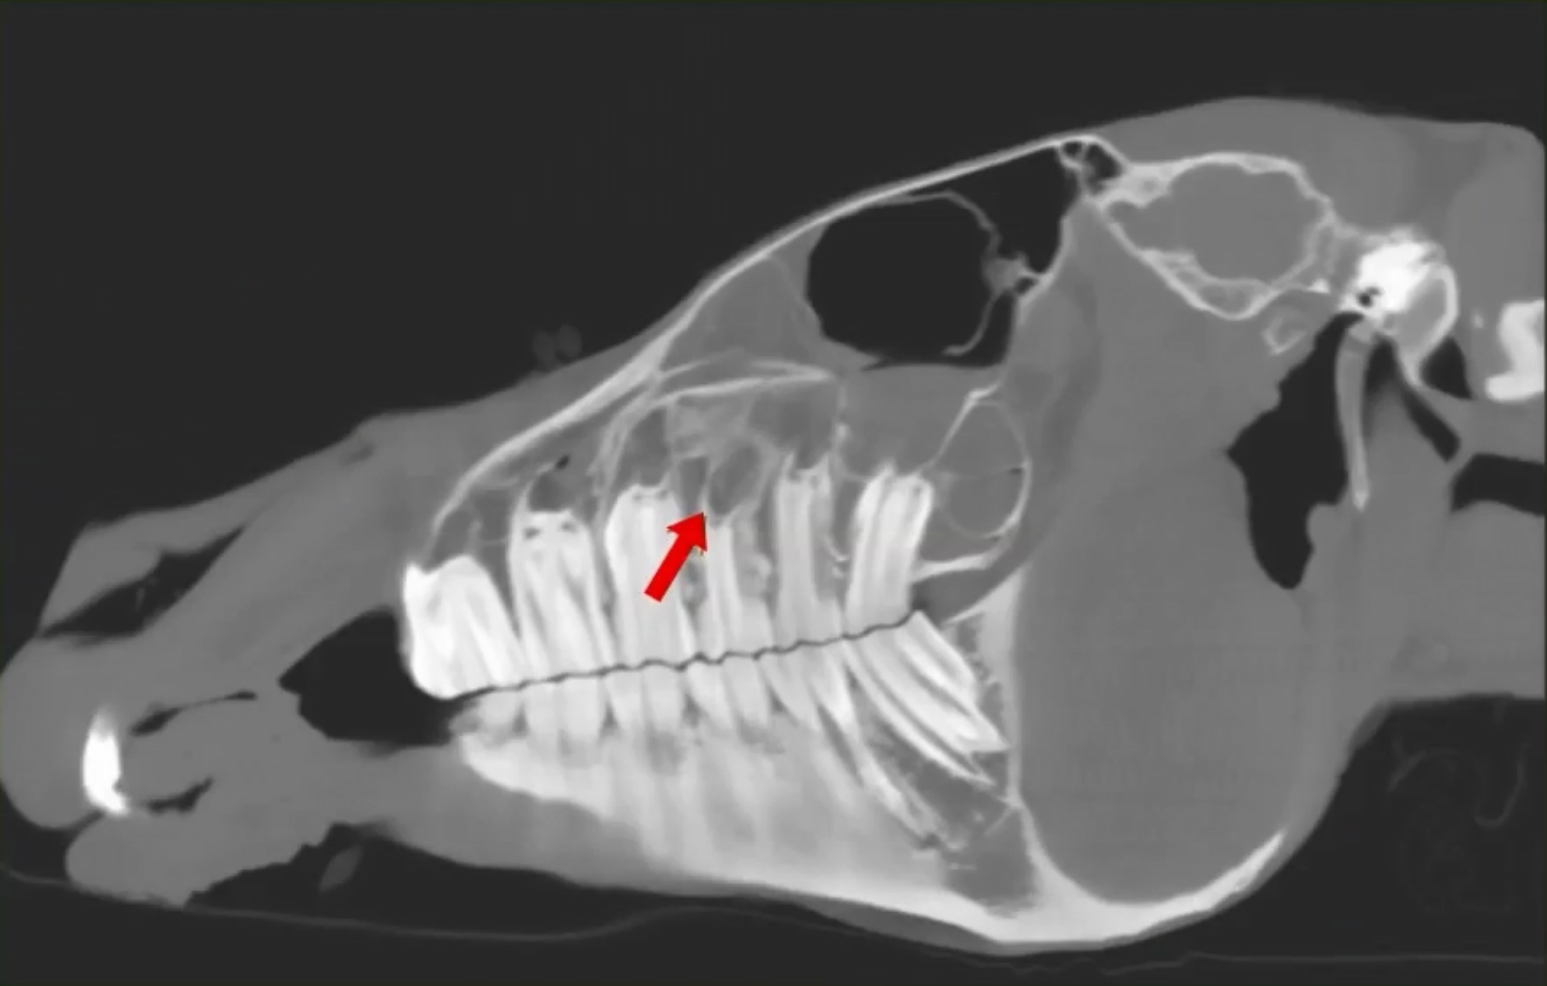

Head & Neck issues: If your horse is scheduled for a head scan, a facility handler will lead your horse into special stocks with a cushioned head-board, providing a comfortable platform for your horse to rest during the scan. The operator then positions the CT gantry over the head & neck and initiates the scan. Scans take only 30-40 seconds.. The handler maintains control of the patient throughout the scan with the lead rope. After scanning, your horse will be led back to the stalls to recover from sedation.

• Standing CT Is a superb tool for diagnosing lameness problems in limbs. It is also best-in-class for diagnosing diseases of the head, such as ethmoid hematoma, sinus problems and teeth/jaw problems; and for diagnosis of equine neck diseases, such as osteoarthritis and fractures.